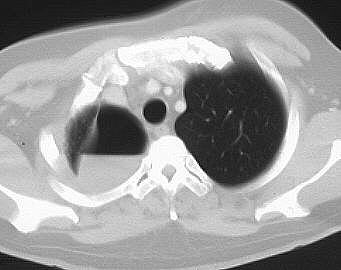

Seropneumothorax rechts